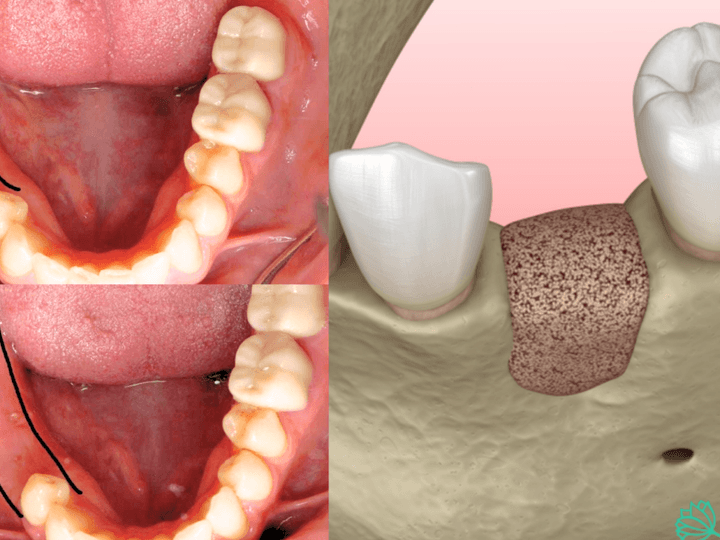

Якщо ж ситуація дозволяє зберегти ретинований зуб і є бажання інтегрувати його в зубну дугу, застосовується ортодонтичне витягування. Цей метод передбачає поетапне лікування: спочатку встановлюється брекет-система, далі хірургічним шляхом відкривається доступ до ретинованого зуба, після чого він поступово витягується за допомогою спеціальних ортодонтичних тяг.

Такий підхід потребує більше часу та зусиль, однак він дозволяє зберегти зуб, забезпечити правильний прикус, функціональність та естетичну гармонію усмішки.